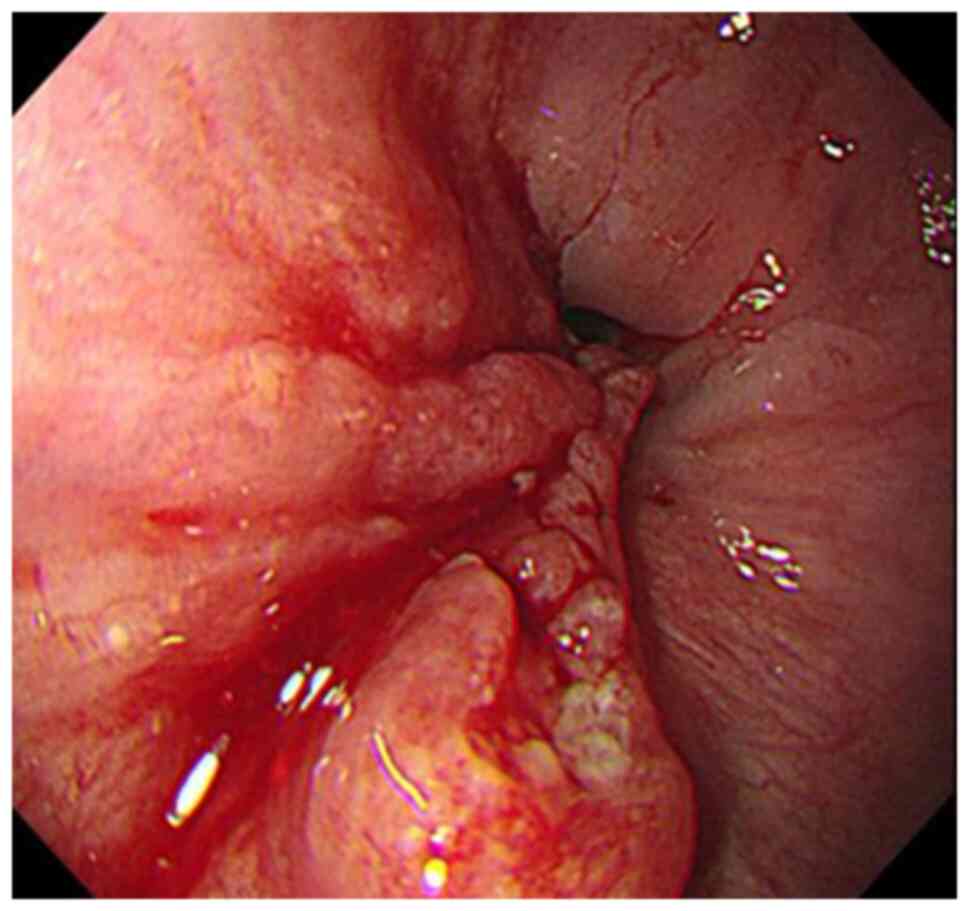

Figure 1

Esophagogastroduodenoscopy. A tumor encompassing 75% of the circumference of the lower thoracic esophagus. The tumor is located at a position 36 to 39 cm from the incisors.

An esophagogastroduodenoscopy revealed a tumor that involved almost the entire circumference of the esophagus at a site 36 to 39 cm from the incisors (Fig. 1). An examination of a biopsy using an esophagogastroduodenoscopy revealed squamous cell carcinoma. Two pathologists were involved in this evaluation. Computed tomography revealed no obvious invasion of the surrounding esophageal cancer, and the 101R lymph node was enlarged (clinical T2N1M0, stage II; according to the eighth edition of the Union for International Cancer Control system) (14). A 22x20 mm-sized mass was also detected in the pancreatic tail. Contrast enhancement of the tumor was poor during the early phase and exhibited progressive enhancement (Fig. 2). The detected levels of tumor markers were as follows: i) carcinoembryonic antigen, 3.3 ng/ml (reference range, <4.1 ng/ml); ii) CA19-9, 2 U/ml (reference range, <37 U/ml); iii) squamous cell carcinoma antigen, 1.9 ng/ml (reference range, <2.5 ng/ml); iv) DUPAN-2, 25 U/ml (reference range, <150 U/ml), and v) Span-1, 6.8 U/ml (reference range, <30 U/ml). Due to esophageal stricture, an endoscopic ultrasound-guided fine needle aspiration biopsy (EUS-FNA) could not be performed, and the neoadjuvant therapy was not administered, since primary pancreatic cancer could not be excluded. Subsequently, it was decided that the patient should undergo a resection of both the primary cancer in the esophagus and the metastatic tumor in the pancreatic tail.